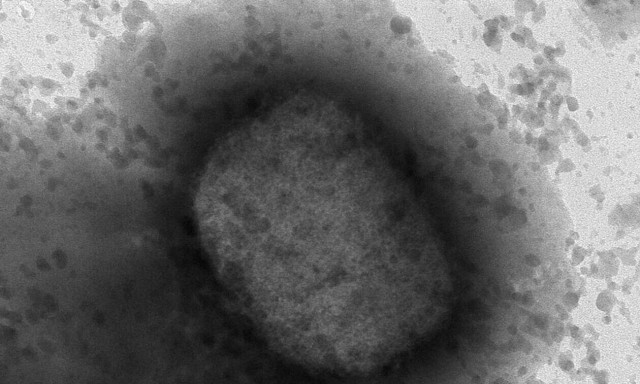

ΕΥΛΟΓΙΑ ΤΩΝ ΠΙΘΗΚΩΝ

Ευλογιά των πιθήκων: Πώς μεταδίδεται - Τα συμπτώματα